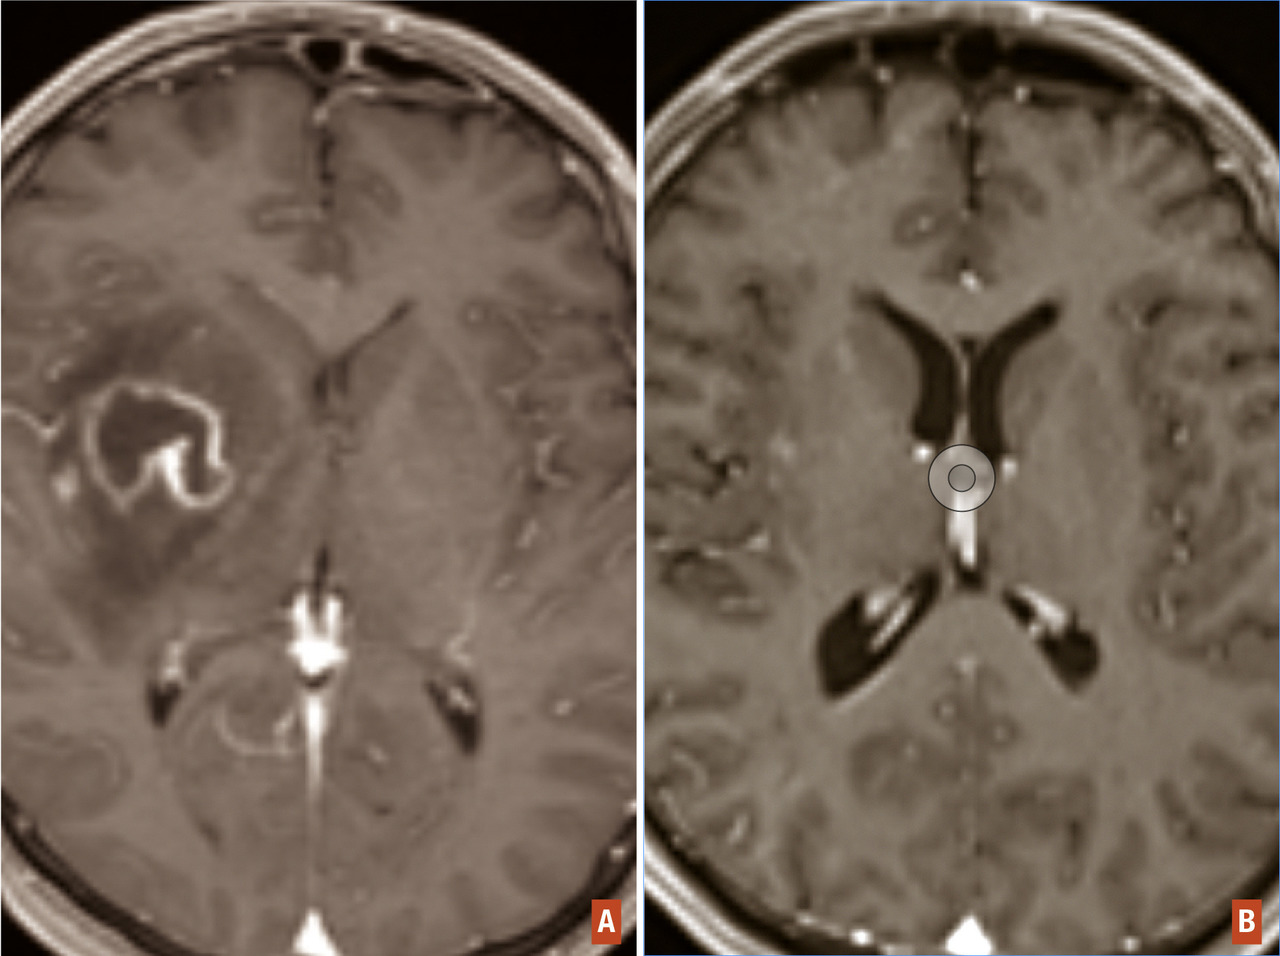

La dissémination métastatique d’un cancer systémique ou d’une tumeur cérébrale primitive aux méninges peut se mani­fester de façon aiguë sous la forme d’un syndrome méningé (céphalées, vomissement, raideur de nuque), d’une hypertension intracrânienne ou d’un syndrome confusionnel, mais plus souvent elle se manifeste de façon plus insidieuse, par l’installation subaiguë de troubles cognitifs, de troubles de l’équilibre, de douleurs radiculaires (névralgies cervicobrachiales, lombosciatiques), d’un syndrome de la queue de cheval, d’une atteinte multiple de nerfs crâniens. L’IRM cérébrale sans et avec injection de gadolinium peut montrer un envahissement des espaces leptoméningés prenant le contraste de façon diffuse ou localisée ainsi qu’une dilatation des ventricules témoignant d’une gêne à la résorption du LCR (hydrocéphalie communicante (fig. 7). L’IRM médullaire peut aussi révéler des lésions étagées au niveau des méninges prenant le contraste volontiers associées à des lésions nodulaires des racines lombosacrées (« métastases en goutte » ou « drop metastase »). La ponction lombaire quand elle est possible confirmera le diagnostic par la présence en anatomopathologie de cellules tumorales. Il existe classiquement une hyperprotéinorachie et une hypoglycorachie. Cependant, la ponction lombaire peut être négative et il faudra répéter l’examen avec une quantité de liquide suffisante pour optimiser la chance de trouver des cellules tumorales.